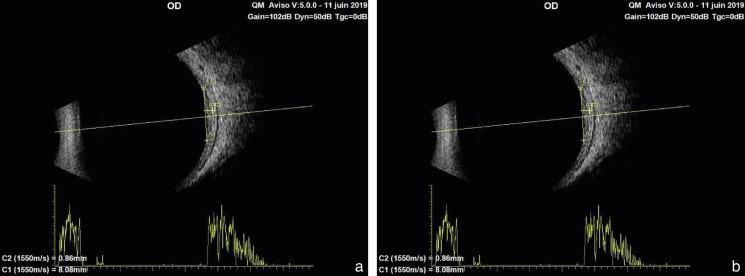

L'échographie permet de mesurer l'épaisseur de la tumeur. Pour les tumeurs périphériques, on aura soin de demander au patient d'orienter son regard en nasal quand la tumeur est nasale, ou en temporal quand la tumeur est temporale. L'essentiel est de toujours avoir une ligne hyperéchogène en surface qui assure que l'on est bien perpendiculaire à l'axe de la tumeur. Par convention, l'épaisseur est en principe mesurée jusqu'à la sclère. Lorsque l'on compare différentes mesures échographiques, il faut vérifier que les repères ont été bien positionnés de la même façon sur chaque examen. L'échographie permet également de dépister une atténuation des ultrasons qui serait un facteur de risque de dégénérescence, mais qui est plus facile à mettre en évidence dans les lésions de plus de 3 mm d'épaisseur.

La taille du nævus est un critère important qui le rend suspect si l'épaisseur est supérieure à 2 mm et, dans certaines séries, supérieure à 1,5 mm et/ou si le diamètre est supérieur à 7 mm ou 5 mm selon les études. Le diamètre des petits mélanomes est plutôt surestimé en échographie et serait mieux analysé en OCT [1]. L'épaisseur de la lésion est plus précisément mesurée par échographie. Une lésion dont la taille est comprise entre 6 et 8 mm de diamètre et 1,5 et 3 mm d'épaisseur peut correspondre à un gros nævus ou à un petit mélanome débutant.